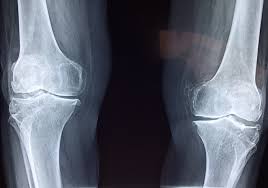

무릎 연골 손상 증상 진단 방법

무릎 연골 손상 증상을 진단하기 위해서는 전문의의 상담과 검사가 필요합니다. X-ray나 MRI와 같은 진단 방법을 통해 손상의 범위와 정도를 확인할 수 있으며, 이는 적절한 치료 방법을 결정하는 데 중요한 역할을 합니다. 초기 진단이 이루어지지 않으면 무릎 연골 손상 증상이 악화되어 퇴행성 관절염으로 이어질 가능성이 높기 때문에, 무릎 통증이 지속되면 즉시 의료기관을 방문해야 합니다.